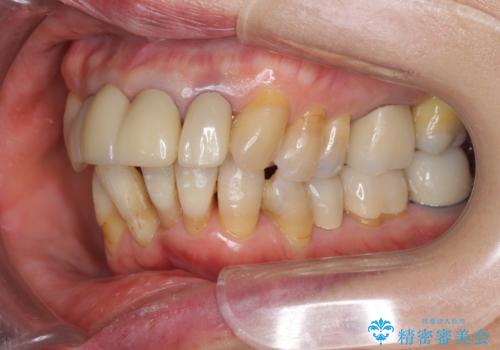

- 上顎前歯の黒ずみの改善、下顎前歯の十度なガタつき、矯正治療とセラミック治療を含む全体的な治療を希望され来院されました。

銀歯を高強度の仮歯に替えたのち、下顎前歯のみの部分矯正→全体的なマウスピース矯正治療(インビザライン)→最終的なセラミック治療と治療を進めます。

矯正治療と目立つ銀歯のやりかえを行ったことでかみあわせだけでなく、審美性・清掃性も改善し口腔内の環境を劇的に改善することができました。